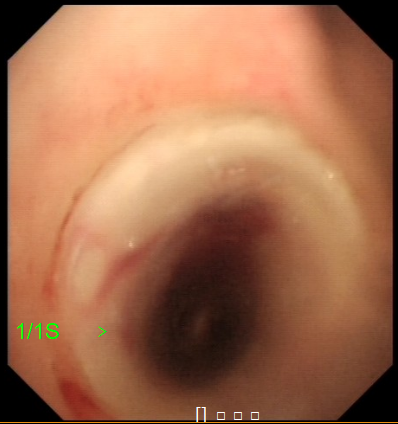

冯起校主任团队在麻醉科的配合下,充分评估病情、做足风险预案,2022年6月23日下午在内镜中心为患者成功放置了硅酮支架,全程只用了20多分钟,术后巨大瘘口被完全封堵,患者可以恢复正常饮食而不用担心食物从瘘口掉进气道里,从根本上解决了患者的饮食和营养需求,反复的肺炎也从源头得到了控制,极大提高了患者的生活质量,也为后续的治疗创造了条件。

图2:硅酮支架置入后瘘口完全被封堵,气道通畅